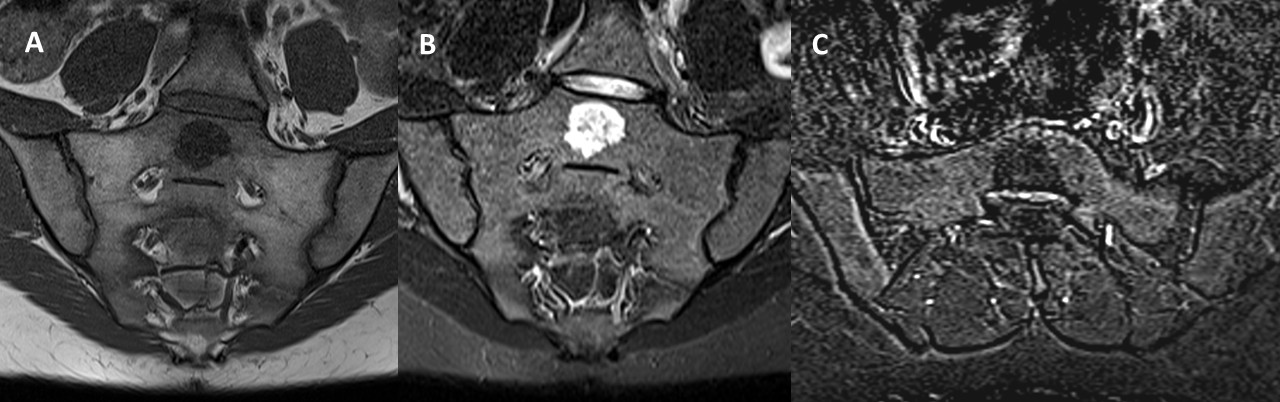

MRI (Fig.1) revealed an incidental nodule on the posterior aspect of the S1 vertebral body. The lesion was well-defined, regular, and measured 30 mm, with heterogeneous T2 hyperintensity and T1 hypointensity. No evidence of intralesional fat, surrounding edema, diffusion restriction, or post-contrast enhancement were observed.

Figure 1: Coronal oblique T1-weighted (A), STIR (B) and axial oblique T1 fat saturated post-contrast subtraction (C) MRI images demonstrate a lesion in the midline of the S1 vertebral body with heterogeneous T2 hyperintensity and T1 hypointensity. No evidence of post-contrast enhancement or surrounding edema was observed.